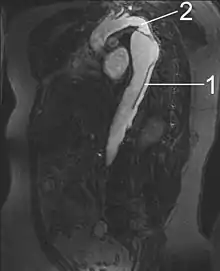

MRI

- Aorta descendens with dissection

- Aorta isthmus

Magnetic resonance imaging (MRI) is also used for the detection and assessment of aortic dissection, with a sensitivity of 98% and a specificity of 98%. An MRI examination of the aorta produces a three-dimensional reconstruction of the aorta, allowing the physician to determine the location of the intimal tear and the involvement of branch vessels, and to locate any secondary tears. It is a noninvasive test, does not require the use of iodinated contrast material, and can detect and quantitate the degree of aortic insufficiency.

The disadvantage of the MRI scan in the face of aortic dissection is that it may be available only in larger hospitals, and the scan is relatively time-consuming, which could be dangerous in people who are already very unwell. Due to the high-intensity magnetic fields used during MRI, it cannot be used on individuals with metallic implants. In addition, some individuals experience claustrophobia while surrounded by the MRI magnet.